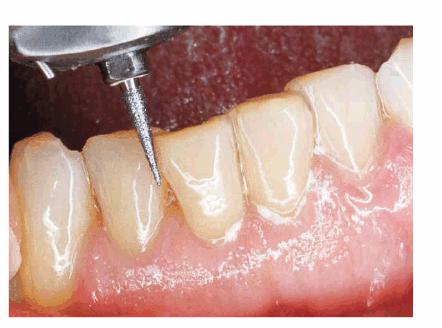

Figures 29-5A and B show a patient who did not like the

appearance of her front teeth. She felt that her maxillary central incisors

were too dark and too short. Cosmetic resin bonding was chosen as the treatment

of choice because of the immediacy of the result. Figures 29-5C and D show how the teeth were both lightened

and lengthened to provide a younger-looking smile line.

Figure 29-5A and B: This 78-year-old lady had shortened and darkened maxillary central incisors. (Reproduced with permission from Goldstein RE. Change your smile. 3rd edn. Carol Stream, IL: Quintessence, 1997:242.)

Figure 29-5C and D: Composite resin bonding was done to lengthen and lighten the central incisors. (Reproduced with permission from Goldstein RE. Change your smile. 3rd edn. Carol Stream, IL: Quintessence, 1997:242.)